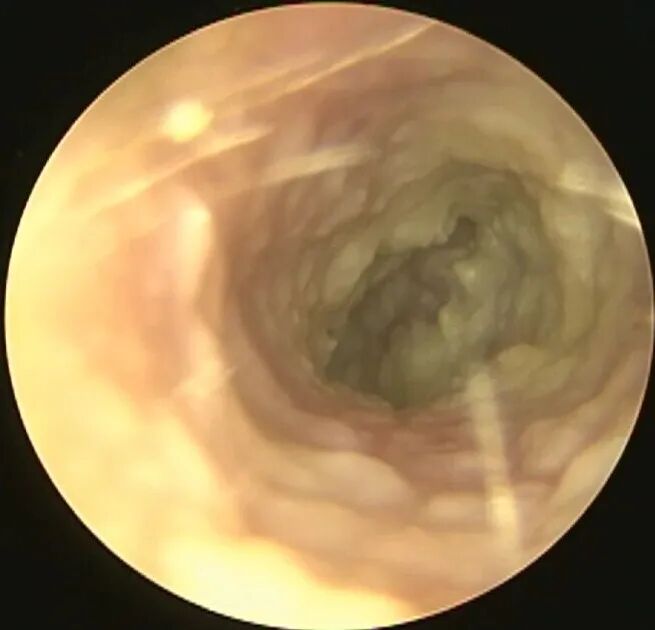

但是有时虽然看不到菌毛和孢子,但实际上也是真菌感染,比如: